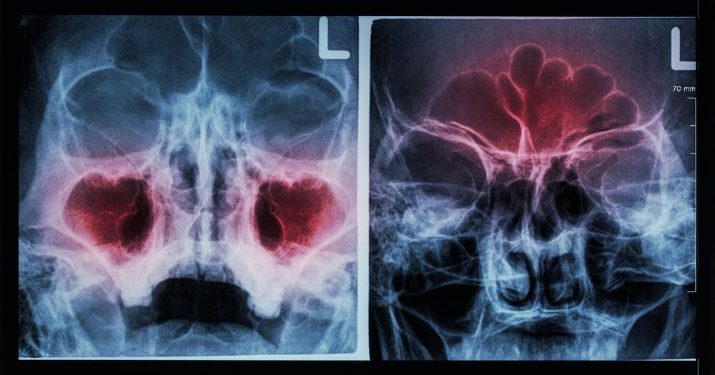

Sinusitis is an inflammation of the lining of your sinuses, which are hollow areas within the bones of the face that are connected to your nasal passages. It is often caused by viruses, but it can also be a result of bacteria and sometimes fungus.

The symptoms of sinusitis are characterized by nasal congestion, facial pain or pressure, and a discharge from the nose that is thick green or yellow. These symptoms usually go away after a few days, but they can continue for longer periods of time in chronic sinusitis.

Your doctor can diagnose sinusitis using a detailed history and physical examination. He or she can determine whether your mucus is purulent and can look at your sinuses with a microscope to help distinguish bacterial from viral sinusitis.